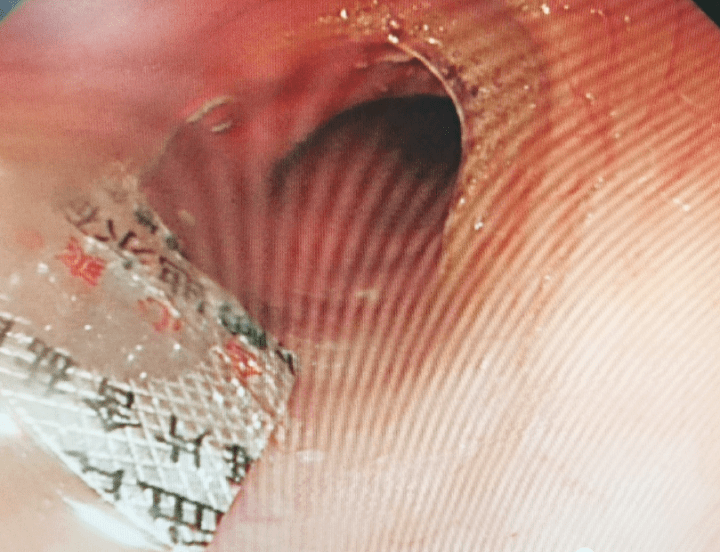

脾胃病科副主任叶蔚给老王做了内镜室手术 。 在老王的食管内 , 看到了一块大小约1cm*1cm大小的方形包装盒及药片 , 锋利的外包装横亘于食管 , 已经对食管粘膜造成了一定的损伤 。

文章图片

好一番折腾 , 带包装的药片被钳出了食管外 。